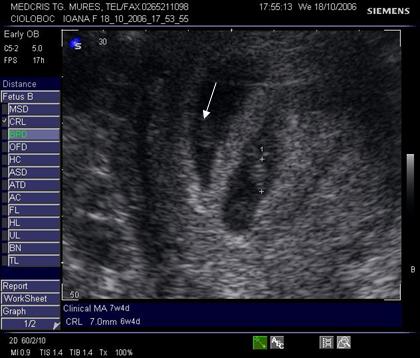

Fig nr 40 .

Sarcina 5 sapt monoamniotica, cu doua vezicule viteline si un embrion (cu o

sageata ). Vezicula vitelina normala ca marime ( cu linie ) apartine embrionului vizibil. Vezicula

vitelina anormal de mare ( cu doua sageti ) si fara embrion indica o sarcina

gemelara , cu lipsa dezvoltarii unui

embrion